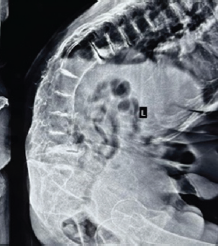

Recurrent Familial Normophosphatemic Tumoral Calcinosis: A Case Report

Shibanand Buddhia , Tushar Ranjan Dalei , Kumud Badhu Sahoo , Ravindra Kumar Chowdhury

………………………………p.217-222